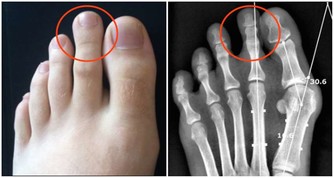

TOP1爬樓梯

相關數據顯示,在60歲以上的老人跌倒中,

超過51%與爬樓梯相關,爬樓梯每年導致2萬人死亡。

進入老年後,人體肌肉會減少3%-5%,關節開始退化,上下樓梯或者爬山時,

膝關節承受人體重量是平時的3-5倍,這會加重關節老化。